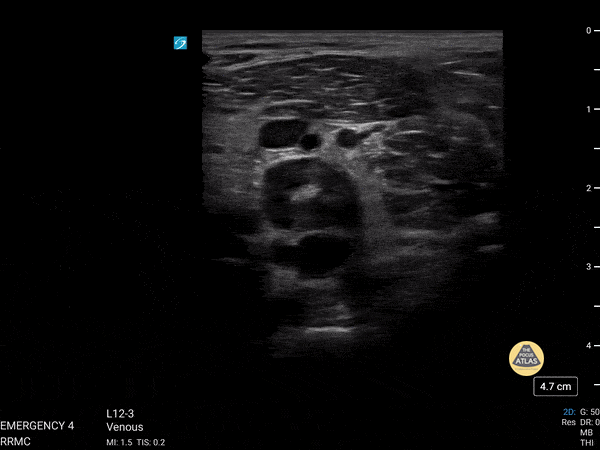

Vascular - Popliteal DVT

This is of a 52 year old male who presented to the emergency department complaining of leg pain and erythema while at work. He was evaluated prior to his arrival to the emergency department and was noted to have an elevated d-dimer level. Point of care ultrasound was performed starting from the great saphenous vein and common femoral vein, descending along his femoral vein. Initial compression did not reveal any thrombus until arriving at his popliteal vein which revealed a non-compressible vein due to a large thrombus. Dr. Christopher Paulo, DO, PGY-1 Riverside Regional Medical Center Emergency Medicine Program (Newport News, VA)